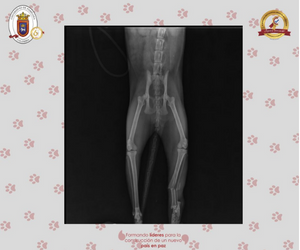

• Radiología digital

GALERÍA FOTOGRÁFICA: NUESTROS PACIENTES